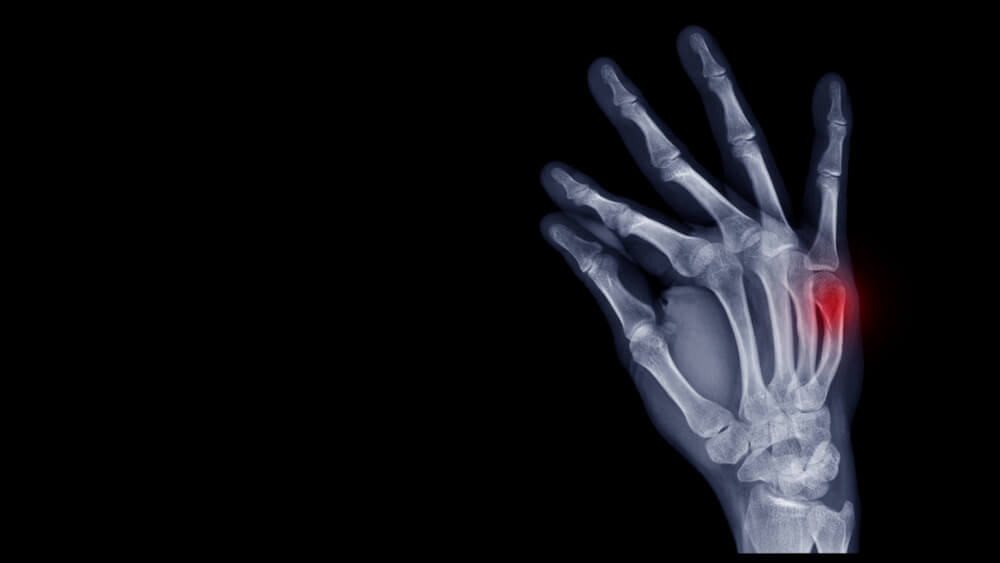

What To Do After Boxer’s Fracture?

What Happens If You Don’t Fix A Boxer’s Fracture?

What Are The Long Term Effects Of A Boxer’s Fracture?

How Long Does It Take For A Boxer’s Fracture To Fully Heal?

What Is The Fastest Way To Heal A Boxer’s Fracture?